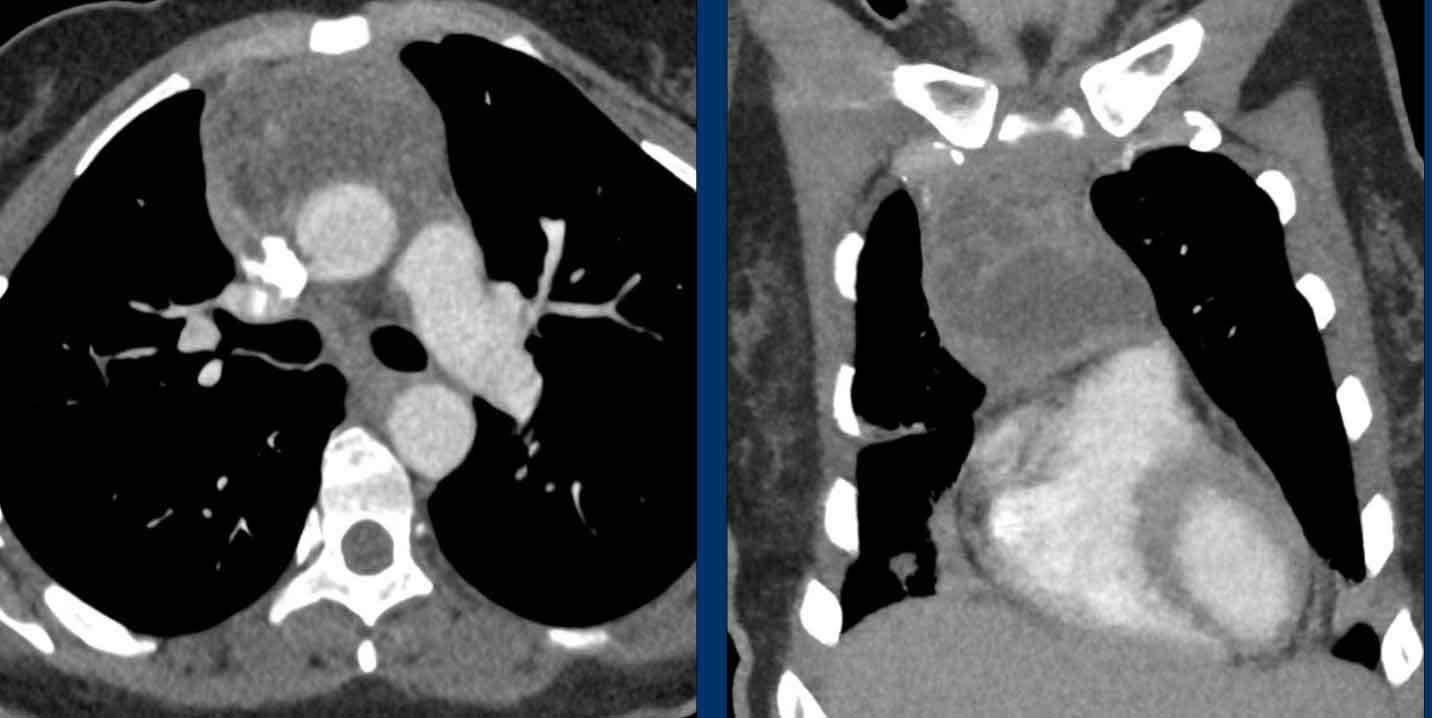

Mặc dù không thực sự cần thiết, MRI vẫn được thực hiện.

Hình ảnh

Hình ảnh chuỗi xung gradient-echo nhanh pha đối (out-of-phase) cho thấy sự mất tín hiệu như dự kiến.

CT cho thấy tuyến ức trở về bình thường sau khi điều trị bệnh Graves.

Khi đo cường độ tín hiệu, bạn sẽ nhận thấy sự sụt giảm cường độ tín hiệu.

Tỷ lệ phần trăm sụt giảm tín hiệu này được gọi là chỉ số cường độ tín hiệu (SII).

Chỉ số cường độ tín hiệu

Chỉ số cường độ tín hiệu (SII) là lượng tín hiệu bị mất đi chia cho lượng tín hiệu ban đầu.

SII lớn hơn 9% có độ nhạy và độ đặc hiệu 100% trong chẩn đoán tăng sản tuyến ức.

SII đáng tin cậy hơn so với tỷ số dịch chuyển hóa học.

Trong trường hợp này, SII là 77%.